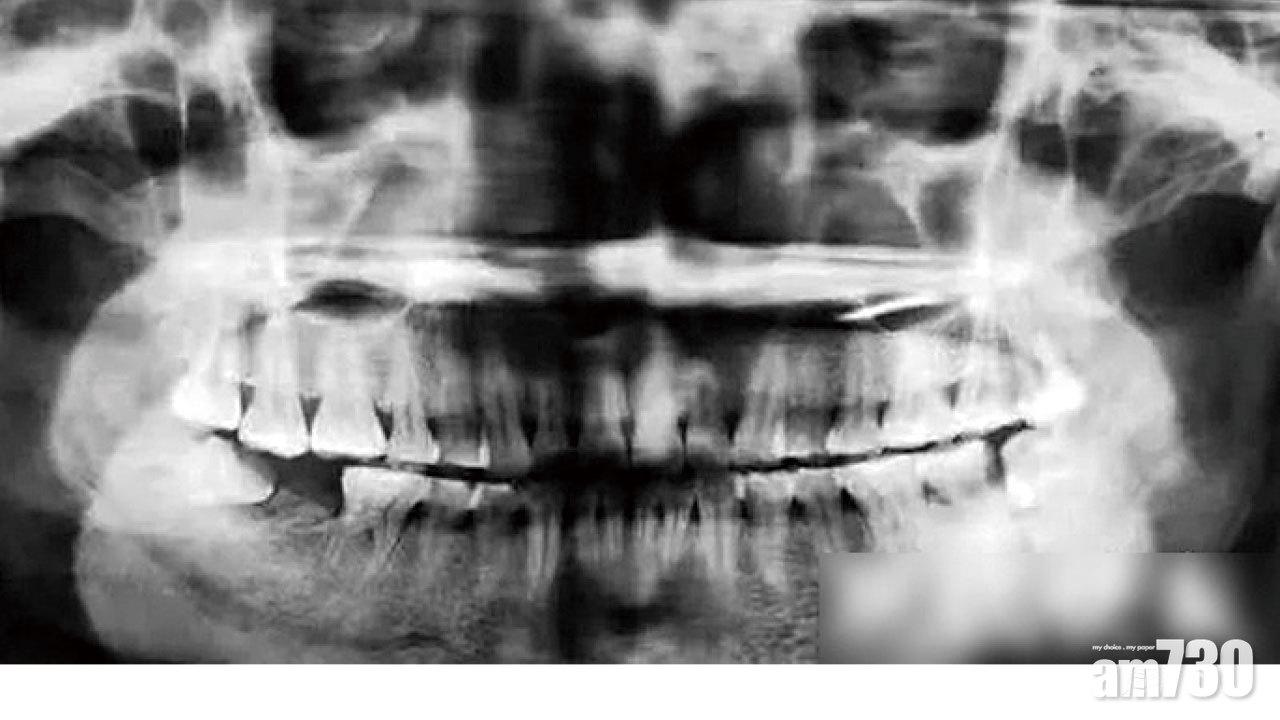

方女的牙齒狀況。(互聯網)

該院口腔科主任醫師黃錦華表示,方女平時不注意口腔衛生,出現智慧齒冠周炎,又無及時治療,導致牙槽骨破壞缺損,面頰被膿腫穿通,涉事智慧齒及前面牙齒均已壞死,兩者都要拔除。報道指,方女已經拔除壞死牙齒,預計一個月後面頰痊愈,半年後再種牙。